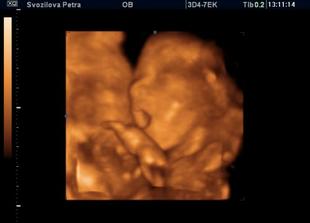

Nase miminko